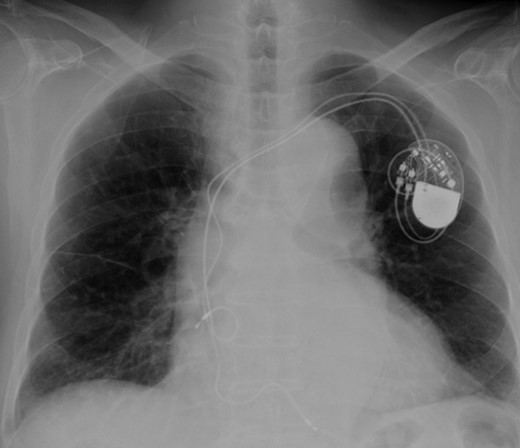

Eight years ago, a DDD pacemaker was implanted in an elderly man due to complete atrioventricular (AV) block. The pacing sites were the appendage of the right atrium and the apex of the right ventricle (Fig. 1) subsequently he suffered PICM with an LV ejection fraction of 37% and obvious dyssynchrony. He had chronic heart failure of NYHA II. Suddenly, the patient developed fever and complained of difficulty eating. Transthoracic echocardiography showed a vegetation (11 × 12 mm2) at the pacemaker leads, and this vegetation was also attached at the tricuspid valve (Fig. 2). Laboratory examination showed elevated white blood cell count and C reactive protein levels. He was diagnosed with PAIE, although the peripheral blood cultures showed no bacteria. After antibiotic therapy, laboratory examination showed decreasing inflammation parameters, but the size of the vegetation remained stable.

A vegetation on the tricuspid valve (arrow). Transthoracic echocardiography shows a vegetation (11 × 12 mm2) attached at the tricuspid valve.